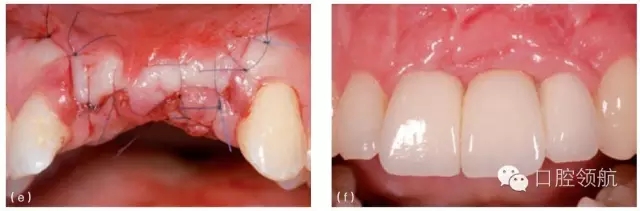

第二種方法是拆除冠和基臺(tái)后行軟組織移植,軟組織瓣冠向復(fù)位部分或完全覆蓋種植體(圖8.23a~e)。愈合后,可能需要二期手術(shù)重新連接基臺(tái)和冠。該方法的優(yōu)點(diǎn)如下:

圖8.23 (a)右上頜側(cè)切牙(7號(hào)位點(diǎn))種植體和冠初診時(shí)情況。約有3mm的黏膜退縮,種植體金屬領(lǐng)圈暴露。(b)第一步,拆下冠和基臺(tái),讓種植體2周時(shí)間的自然愈合。(c)做半厚瓣翻瓣,結(jié)締組織移植至種植體并進(jìn)行瓣的冠向復(fù)位。面觀顯示4周的愈合期后種植體完全埋在黏膜下。(d)做小切口,足以安裝錐形基臺(tái)即可。(e)治療和粘結(jié)新冠3年后,原先的黏膜退縮已成功恢復(fù),組織健康穩(wěn)定。

當(dāng)重新連接基臺(tái)和冠以后,就可以增加唇面的軟組織量。

在拆下基臺(tái)和冠以后,種植體唇腭向植入位置不佳比較容易確定。臨床醫(yī)生從而可以判斷軟組織移植是否有效,同時(shí)可以如實(shí)告知患者。

缺點(diǎn)是治療前必須拆下冠和基臺(tái)。如果是粘結(jié)固位冠,就得把冠破壞。同時(shí)患者需在治療過(guò)程中戴暫時(shí)冠,可能會(huì)持續(xù)幾個(gè)月。